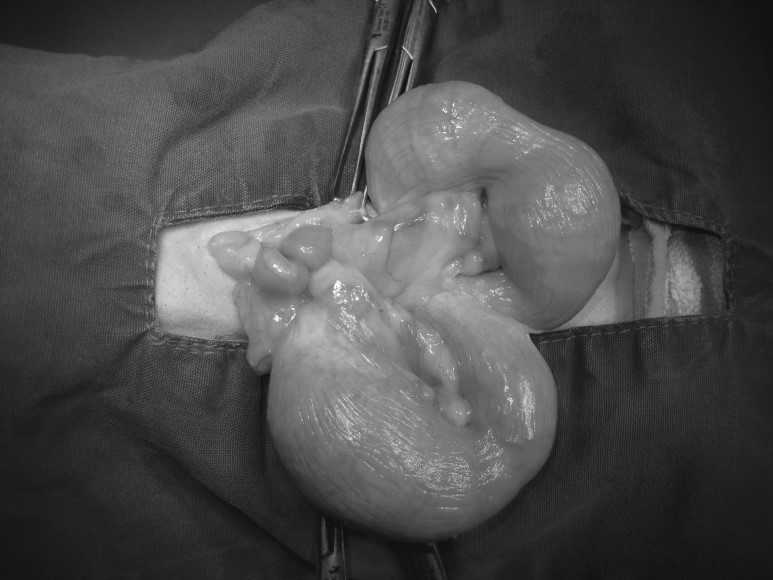

자궁 축농증 고름이 상당히 쌓여있는 자궁에서 즉시 응급 수술이 필요할 것 같았습니다.혈액 검사 상 염증의 수치가 높은 것 이외에 특이점은 없었기 때문에 바로 수술을 시작했습니다.

수술 중 충격을 방지할 수 있는 응급약을 사용하면서 재빨리 자궁을 떼어냈습니다.